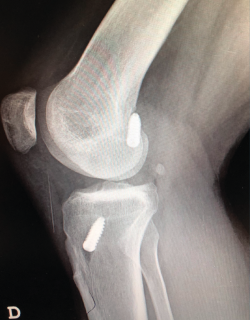

Figura 1. Laxitud en el cajón anterior. Radiología forzada.

Desde el punto de vista clínico, se consideran motivo de revisión quirúrgica aquellos casos en los que exista un desplazamiento anterior comparado con el contralateral mayor de 5 mm, pivot shift de alto grado, dolor, inflamación, sensación subjetiva de inestabilidad y limitación funcional para las actividades de la vida diaria o deportiva(9,10). Algunos autores han rebajado esta cifra a 3 mm con respecto a la rodilla contralateral o 10 mm de desplazamiento absoluto en el plano sagital(11)(Figura 1).